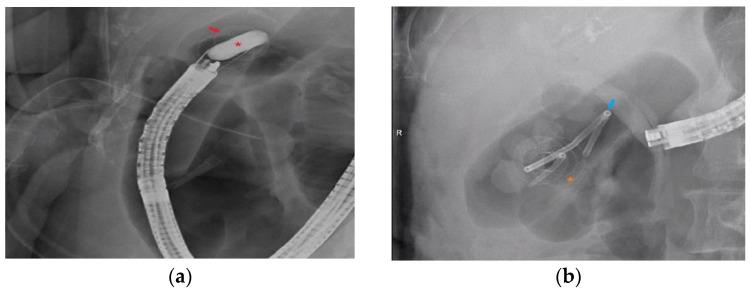

Endoscopic ultrasound-guided gallbladder drainage (EUS-GBD) is an alternative to surgery for acute cholecystitis (AC) in poor operative candidates. However, the role of EUS-GBD in non-cholecystitis (NC) indications has not been well studied. We compared the clinical outcomes of EUS-GBD for AC and NC indications. Consecutive patients undergoing EUS-GBD for all indications at a single center were retrospectively analyzed. Fifty-one patients underwent EUS-GBD during the study period. Thirty-nine (76%) patients had AC while 12 (24%) had NC indications. NC indications included malignant biliary obstruction ( = 8), symptomatic cholelithiasis ( = 1), gallstone pancreatitis ( = 1), choledocholithiasis ( = 1), and Mirizzi's syndrome ( = 1). Technical success was noted in 92% (36/39) for AC and 92% (11/12) for NC ( > 0.99). The clinical success rate was 94% and 100%, respectively ( > 0.99). There were four adverse events in the AC group and 3 in the NC group ( = 0.33). Procedure duration (median 43 vs. 45 min, = 0.37), post-procedure length of stay (median 3 vs. 3 days, = 0.97), and total gallbladder-related procedures (median 2 vs. 2, = 0.59) were similar. EUS-GBD for NC indications is similarly safe and effective as EUS-GBD in AC.

内镜超声引导下胆囊引流术(EUS-GBD)是手术风险较高的急性胆囊炎(AC)患者的一种手术替代方案。然而,EUS-GBD在非胆囊炎(NC)适应症中的作用尚未得到充分研究。我们比较了EUS-GBD治疗AC和NC适应症的临床疗效。对在单一中心接受EUS-GBD治疗所有适应症的连续患者进行回顾性分析。在研究期间,51例患者接受了EUS-GBD治疗。39例(76%)患者为AC,12例(24%)为NC适应症。NC适应症包括恶性胆管梗阻(=8)、有症状的胆结石(=1)、胆石性胰腺炎(=1)、胆总管结石(=1)和Mirizzi综合征(=1)。AC组技术成功率为92%(36/39),NC组为92%(11/12)(P>0.99)。临床成功率分别为94%和100%(P>0.99)。AC组有4例不良事件,NC组有3例(P=0.33)。手术时间(中位数43 vs. 45分钟,P=0.37)、术后住院时间(中位数3 vs. 3天,P=0.97)和与胆囊相关的总手术次数(中位数2 vs. 2,P=0.59)相似。EUS-GBD治疗NC适应症与治疗AC一样安全有效。